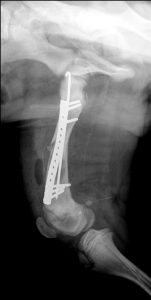

Cette technique est fondée sur la mise en place d’une plaque fine et la plus longue possible, ancrée dans l’os par seulement deux vis sur chaque fragment, occupant les trous les plus éloignés du foyer de fracture.

La plaque est d’abord mise en forme en prenant exemple sur la radiographie du membre controlatéral. Les vis sont insérées dans les 2 premiers et 2 derniers trous de la plaque et serrées sans taraudage préalable.

Pour le fémur, les vis proximales sont proches de l’insertion du vaste latéral, les vis distales proches de la plaque de croissance. Pour le tibia, les vis proximales et distales sont proches des plaques de croissance.

Les vis adjacentes sont insérées dans deux plans différents pour augmenter la résistance à l’arrachage.